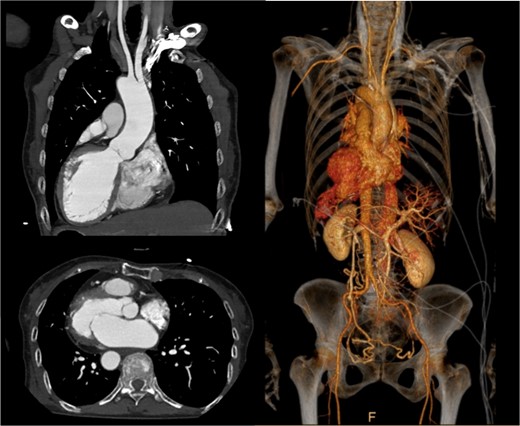

A 75-year-old woman with a history of SIT and dextrocardia was referred to our department for surgical intervention due to severe functional mitral regurgitation (MR) causing heart failure despite medical therapy. Chest X-ray showed dextrocardia and cardiomegaly with a cardiothoracic ratio of 56.1%. ECG showed sinus rhythm at 75 bpm. Contrast-enhanced computed tomography (CT) showed complete situs inversus with mirroring of all organs and no other congenital anomalies (Fig. 1). Transesophageal echocardiography showed a reduced left ventricular ejection fraction of 43% and severe functional MR due to tethering of both leaflets was also observed.

Preoperative contrast-enhanced CT: axial, coronal oblique MIP, and coronal oblique 3D VR images demonstrating situs inversus totalis and dextrocardia.